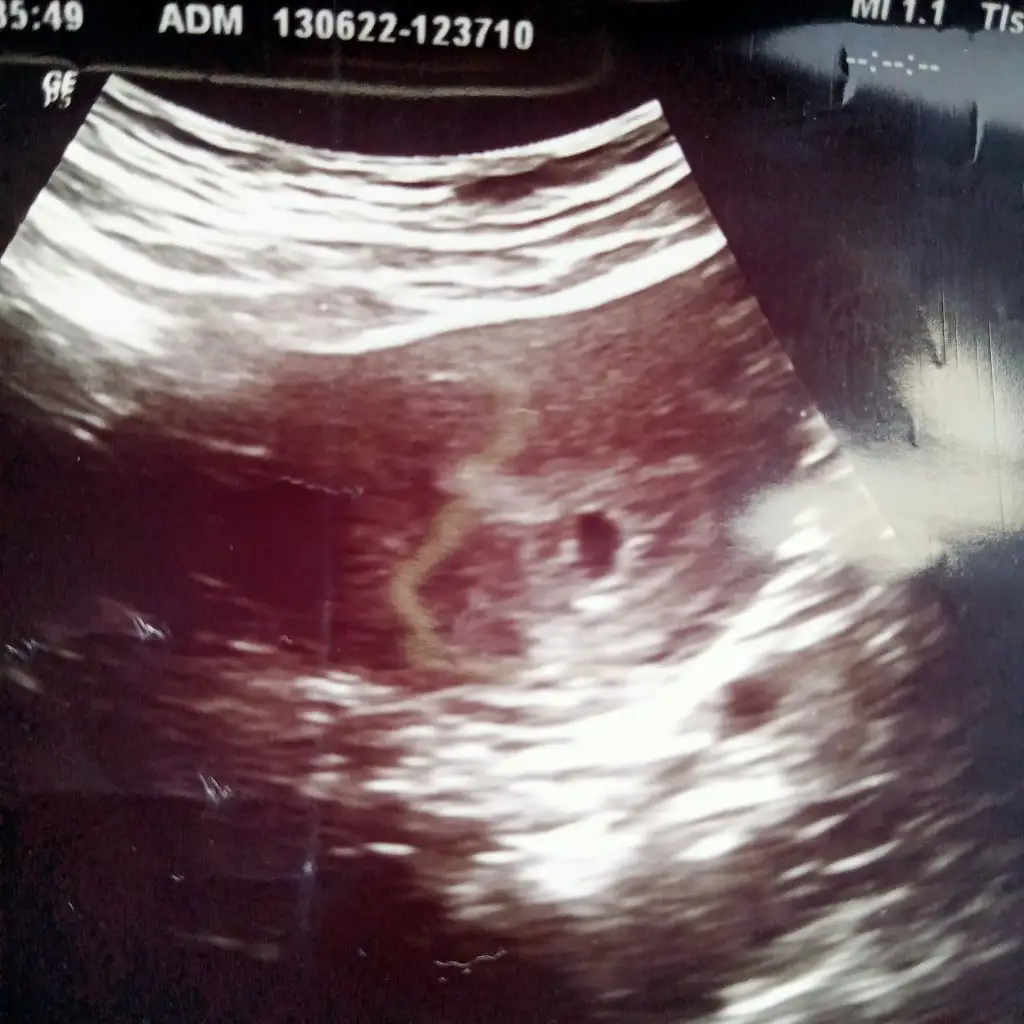

Benimki böyle ama ben 3 hafta once test yaptıgımda negatifti 1 hafta once yaptım pozitif cıktı tuhaf anlayamadım

Ben konuyla alakasız birsey soracam 5 haftalık ama kesenin icinde birşey yok acaba doktor haftayı mı yanlış soyledı burda bakıyorum 6 haftalıklar da kocaman birşy var kesede benim bomboş gorunuyordu

Geç döllenme olabilir belki ya da kişiden kişiye değişir diye düşünüyorum